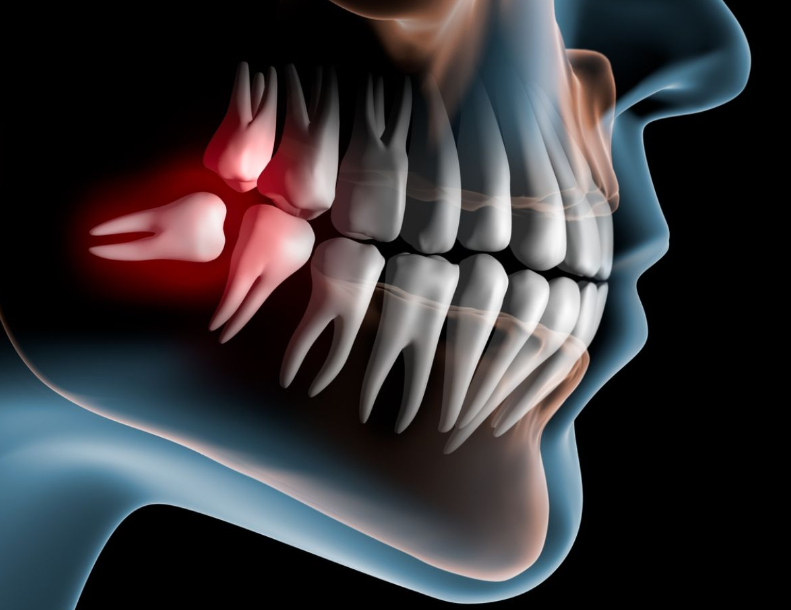

As humans have evolved, our jaws have become smaller. Due to this, there is often not enough space for the wisdom teeth to emerge properly. As a result, they may erupt at an angle or remain impacted (trapped beneath the gums). When they grow at an angle, it’s difficult to clean the area properly, leading to food accumulation. This can cause tooth decay in the wisdom tooth and neighboring teeth, as well as gum inflammation—leading to most of the common issues.

Do I always need to get my wisdom teeth removed

No. Wisdom teeth should only be removed if they are causing any of the following problems-

- Decayed wisdom tooth

- Decay of tooth in front of wisdom tooth (second molar)

Does a wisdom tooth always need to be removed?

If the wisdom tooth has fully erupted in the correct position and has a proper opposing tooth to bite against, it can function well during chewing and does not need to be removed.